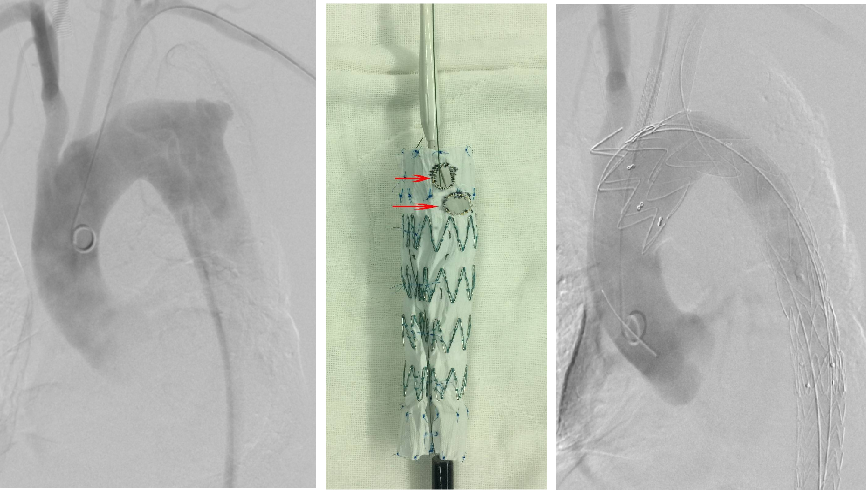

★ 分支支架技术

被视为未来弓上重建的主要方向,有外分支和内分支两种。

Castor单分支支架:中期随访(29个月),106例病例总体技术成功率98.1%,分支通畅率96.2%,再干预率2.8%,死亡率1.9%。

内分支支架:计算流体力学(CFD)分析显示其对血流干扰较外分支明显,但近期疗效相似。外分支支架解剖契合度高,减少血流紊乱和壁面剪切力。